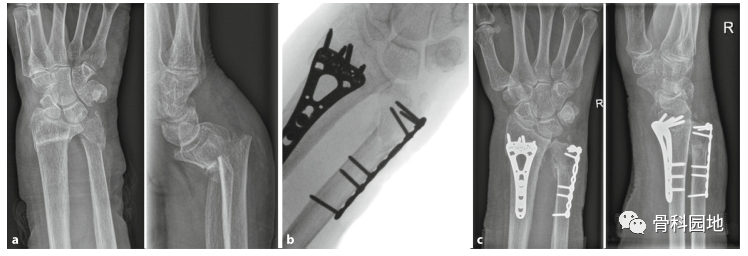

尺远端骨折合并桡骨远端骨折患者术前、术中及术后影像。